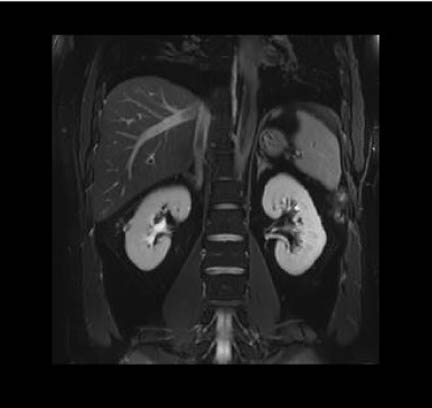

EXCEPTIONAL IMAGE QUALITY

- Best-in-class homogeneity and gradient performance

- World’s largest field of view (60x60x50 cm)

- Motion insensitive sequences for clearer images